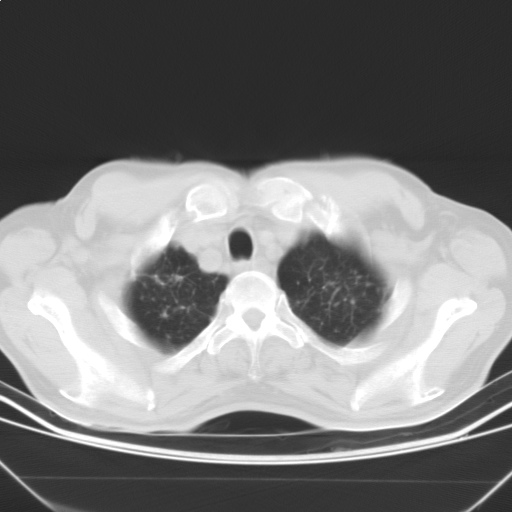

以下是引用随光逐影在2009-5-1 13:53:00的发言:[br]考虑为:1)两肺血行播散型肺结核;2)右肺下叶炎症感染。3)右侧胸膜增厚。